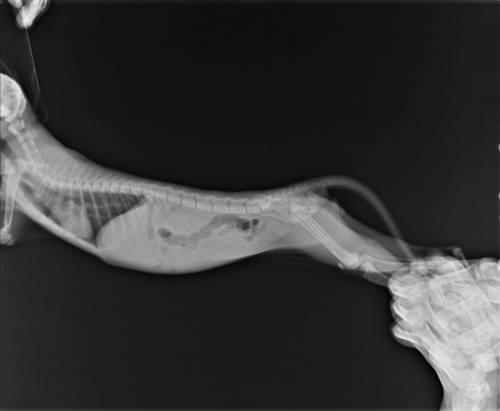

主題: 下埤里急性腎衰竭小幼貓 申請者姓名: 王月香 花色: 申請日期: 2014-07-21 18:15:59 申請者部落格: 申請者臉書網址: 所在縣市/合作醫院: 台北市/極光動物醫院 治療費用: 15250元 需求人數: 17人 已結案 (2014-08-26 15:04:38) 報名人員: Amber Tsai(已付款)、Joy Lin(已付款)、Chris Joan eddy(已付款)、momo(已付款)、NAI(已付款)、wgs(已付款)、lavinia x2(已付款)、Sue Shi(已付款)、Sue Shi(已付款)、philip x2(已付款)、Drew 酷朱(已付款)、Angel Chen(已付款)、Bella Hung(已付款)、ERic YU(已付款)、cynthia(已付款)、 候補人員: 動物病情說明: 小幼貓於6/16因尾巴末端受傷潰爛而被本人救援到,經送醫手術截掉一小段尾巴縫合治療(自費),然後安置吃藥養傷,但是奇怪的是,小幼貓每天哭叫不停,後來出現嘔吐與食慾不振現象,雖再就醫門診,卻未見改善。

6/22清晨小幼貓狀況變差,乃緊急送太僕醫院急診。貓瘟檢驗呈陰性過關,但是血檢報告出來卻嚇我一大跳!白血球五萬、肝指數過高、腎臟指數過高、鉀離子過高,被診斷為「急性腎衰竭」!恐需洗腎治療,天啊!才兩個多月的小朋友怎會這樣呢?本人焦急萬分,乃尋求協會幫忙而轉診到極光動物醫院治療。

極光醫院為小幼貓做詳細檢查後,先以點滴、針劑和口服藥治療,很快地,小幼貓的病情即有改善,血檢的多項報告已趨近正常數字,但仍需注意腎臟方面的變化,且出現的腹瀉狀況亦做糞檢和治療。

小幼貓在極光動物醫院共住院治療6天,出院後繼續服藥,因追蹤病情所需乃再門診一次,接受診察、血檢(一切正常),並做第二次糞檢和驅蟲。

有關在極光動物醫院的住院與門診的醫療費共15,250元,懇請大家幫忙,萬分感激!動物近況說明: 小幼貓目前大小便與吃喝正常,已安排送養當中。